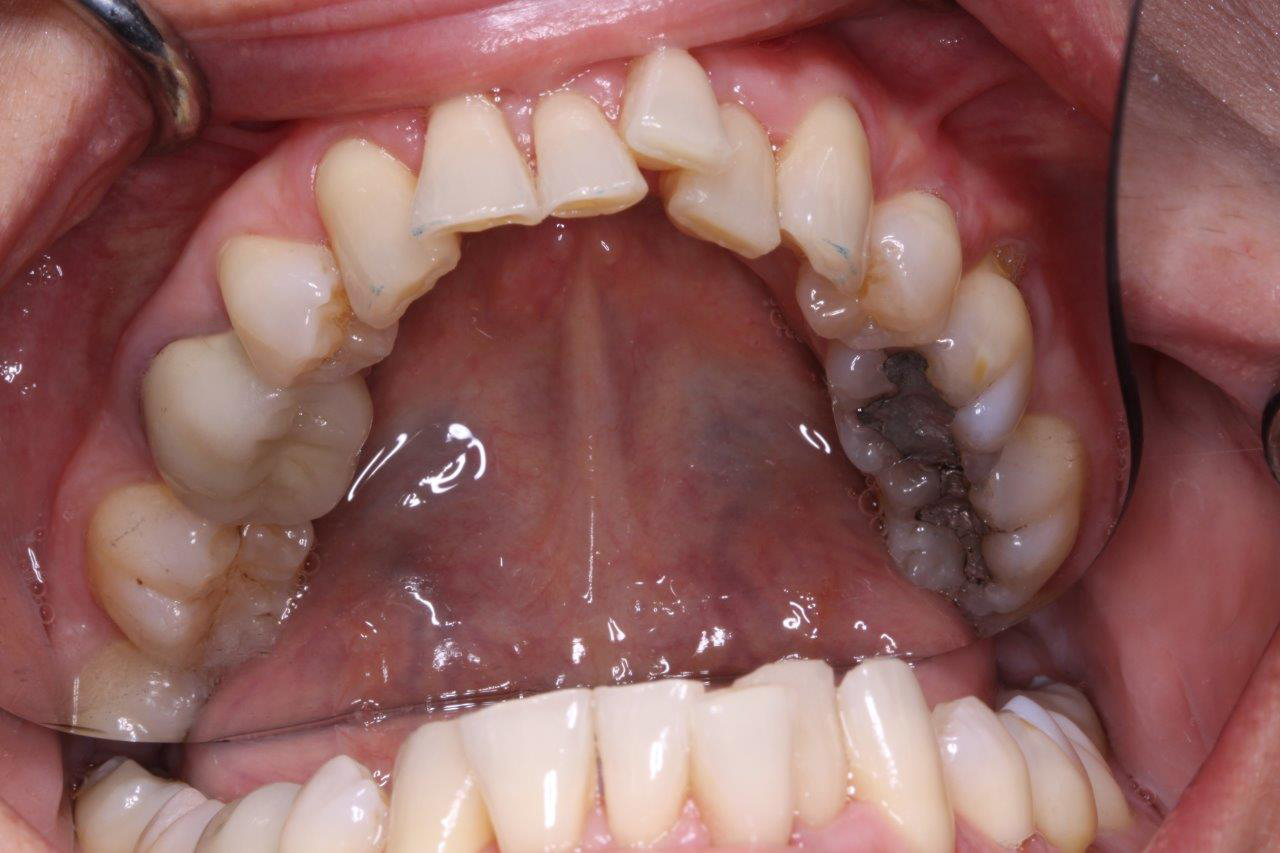

Crowns

Before